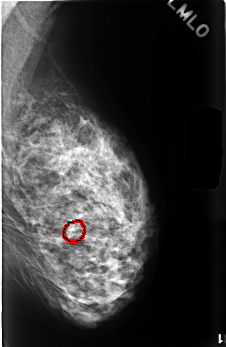

FILE: C_0499_1.LEFT_MLO.OVERLAY

TOTAL_ABNORMALITIES 1

ABNORMALITY 1

LESION_TYPE CALCIFICATION TYPE EGGSHELL DISTRIBUTION N/A

ASSESSMENT 2

SUBTLETY 4

PATHOLOGY BENIGN_WITHOUT_CALLBACK

TOTAL_OUTLINES 1

BOUNDARY